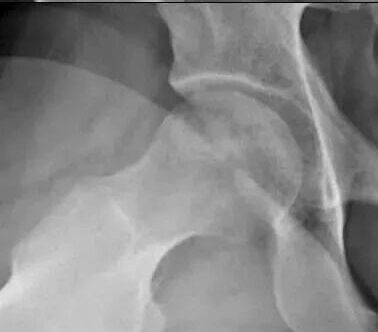

股骨头坏死的保头治疗,其核心在于清除坏死区域、重建血运并植入具有成骨潜能的活性材料。手术技术、材料选择以及对远期并发症的考量,共同决定着保头治疗的最终效果。本文分享一个采用富血小板血浆复合自体松质骨植骨的成功案例,并结合4年随访,探讨临床诊疗要点。 临床病例 患者为男性,25岁,因右侧髋部疼痛来到医院就诊。 术前影像学评估如下: X线检查:股骨头骨密度略有降低。 磁共振检查:右侧股骨头广泛骨髓水肿,提示病变处于进展期。此类影像学表现通常预示病情进展较快,单纯保守治疗或髓芯减压术难以阻挡塌陷的进程。 CT(计算机层析成像)检查:股骨头骨密度明显降低,骨小梁结构受损。这进一步印证了手术干预的必要性。 由于骨密度明显降低且硬化边界清晰,这名患者接受保守治疗或者髓芯减压术为时已晚。 手术方案与材料选择 考虑到这名患者年轻且坏死处于进展期,我和同事为他制定了复合植骨策略。 从髂嵴抽取骨髓,经分离提纯出自体干细胞与高浓度的富血小板血浆。 将高浓度营养因子(经分离提纯后的富血小板血浆富含多种生长因子)与自体松质骨混合,植入坏死区减压后的空腔。 将富血小板血浆制成凝胶,避免植入过程中发生流失。 术后随访与影像学演变 术后X线检查:植入骨填充良好,结构稳定。 术后1年X线检查:植入骨与宿主骨融合良好,遵循“该长则长,该消则消”的生理重塑原则,坏死区得到有效修复。 术后4年X线检查:修复区的骨小梁结构清晰,骨密度显著升高,甚至显示出比自体皮质骨更强的硬化性修复表现。这种力学强度的建立,使远期发生股骨头塌陷的风险极低。需要担心的是远期关节软骨的退变问题。 分析与体会 在对这名患者进行诊疗和随访的过程中,我们有以下体会: 关于死骨清除的边界 清除死骨并非多多益善。死骨与周围的硬化骨往往融为一体,边界难以精确判断。而硬化骨本身是重要的力学支撑结构,术中若伤及“无辜”,破坏了股骨头的原有支撑,反而得不偿失。 关于血运重建 鉴于股骨头内血供的复杂解剖,血运的改善更应侧重于疏通而非重建。通过髓芯减压术打通原有的血供通道,比试图建立一套全新的血运系统更现实、更可行。 关于远期关节软骨退变 这是保头治疗后需要直面的问题。即便骨性修复顺利完成、股骨头形态恢复良好,随着病程进展,缺血导致的关节软骨营养障碍仍可能逐渐显现。 术后4年,这名患者的关节面有裂开迹象,预示着软骨退变乃至骨性关节炎的进程难以完全逆转。 关于保头目标的再认识 保头治疗可延缓关节置换的时间,推迟骨性关节炎的进程。除日常生活中要控制体重、避免剧烈运动和重体力劳动外,对于已经出现关节炎症状的患者,可考虑采用关节腔内注射玻璃酸钠或自体富血小板血浆的方法,改善关节内环境、营养软骨。 关于手术时机 这名患者术前已处于进展期。 临床上,多数患者往往在股骨头即将塌陷时才接受植骨治疗,这在一定程度上决定了保头治疗效果的“有效期”。理想状态下,对于ARCO(国际骨循环研究协会)ⅡB期及更早期的患者,保头治疗成功后有望获得10年乃至更长无关节炎症状的生存期。然而,临床中普遍存在一种现象:不到病变部位即将塌陷,患者往往难以接受尽早进行植骨修复。 总之,富血小板血浆复合自体松质骨植骨为进展期股骨头坏死患者提供了一种更有效的修复策略,能减少骨吸收、缩短骨性愈合时间,从而获得足够的力学支撑。术后需将关节软骨退变纳入长期随访管理范畴,并基于患者的病情、年龄及功能需求开展预期管理,引导患者建立符合自身实际的康复目标与疾病认知。 (作者供职于河南省洛阳正骨医院)